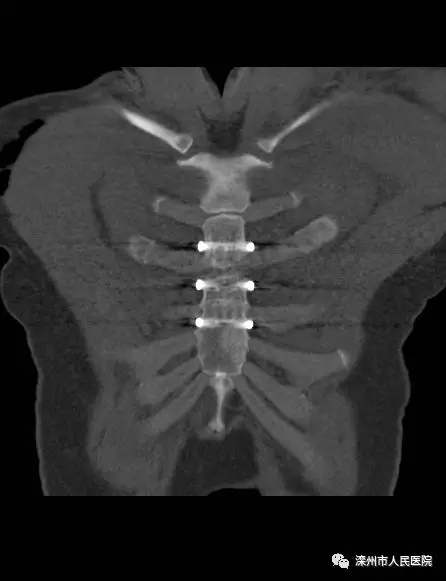

術(shù)后影像

本次手術(shù)改變以往行鋼絲縫合的方法,改用環(huán)抱式胸骨固定器,既減少了組織分離造成的損傷,又避免了胸骨內(nèi)側(cè)穿鋼絲的意外損傷,而且固定效果滿意。